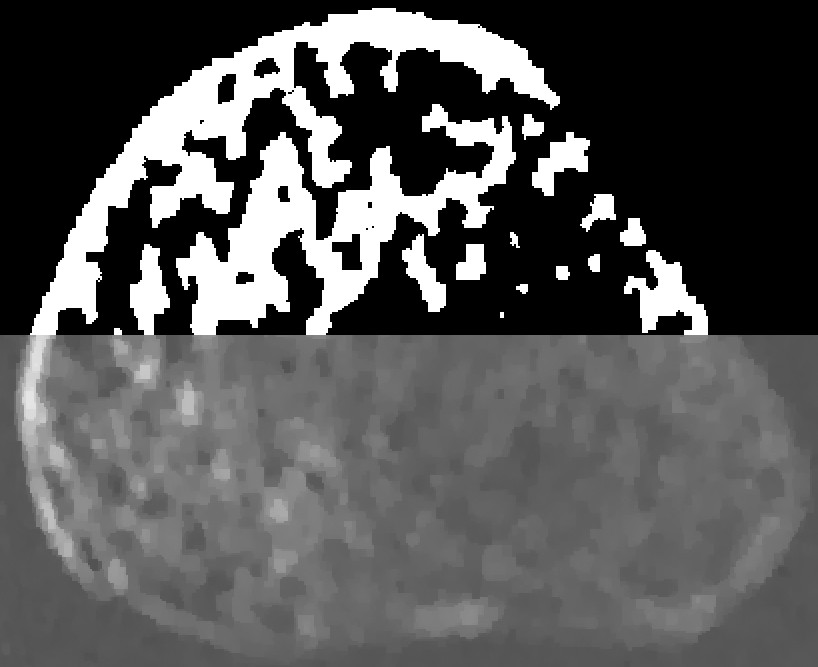

Refer to captionID blurAσ=0.0023𝜎0.0023\displaystyle\sigma=0.0023Refer to captionSI blurBσ=0.0018𝜎0.0018\displaystyle\sigma=0.0018Refer to captionSV blurCσ=0.0019𝜎0.0019\displaystyle\sigma=0.0019Refer to captionanodeSI blurDσ=0.0024𝜎0.0024\displaystyle\sigma=0.0024Refer to captioncathodeSI blurEσ=0.0022𝜎0.0022\displaystyle\sigma=0.00220.0000.0150.0300.0450.060

Figure 6: Physical CBCT reconstructions. Each subfigure shows a portion of the phantom from the edge to one of the line pairs. Each reconstruction has approximately the same noise level (indicated in each subplot in units of mm-1 and denoted by σ𝜎\sigma).

Figure 6 shows the same region-of-interest of five reconstructions, each of which used a different blur model. The three SI blur models are the apparent focal spot size at the center, anode side, and cathode side of the detector. The reconstructions have approximately the same amount of noise (estimated by computing standard deviation in a flat region at the center of the phantom). The line pairs in the SV (6c) and center SI (6b) reconstructions are much sharper than those in the ID reconstruction (6a). That the SI reconstruction line-pairs are roughly as sharp as those of the SV reconstruction suggests that at this distance from isocenter (approximately 4.75cm) the SI approximation is fairly accurate. However, at the edge of the phantom (approximately 7.5cm from isocenter), this assumption breaks down, and the resulting mismatch between the model and the actual blur results in a “ringing” artifact. The anode-side SI blur model (6d) underestimates the blur over most of the detector, reducing ringing compared to the center SI blur model but also reducing the sharpness of the line pairs. The cathode-side SI blur model (6e) overestimates the blur over much of the detector, increasing the ringing artifact.